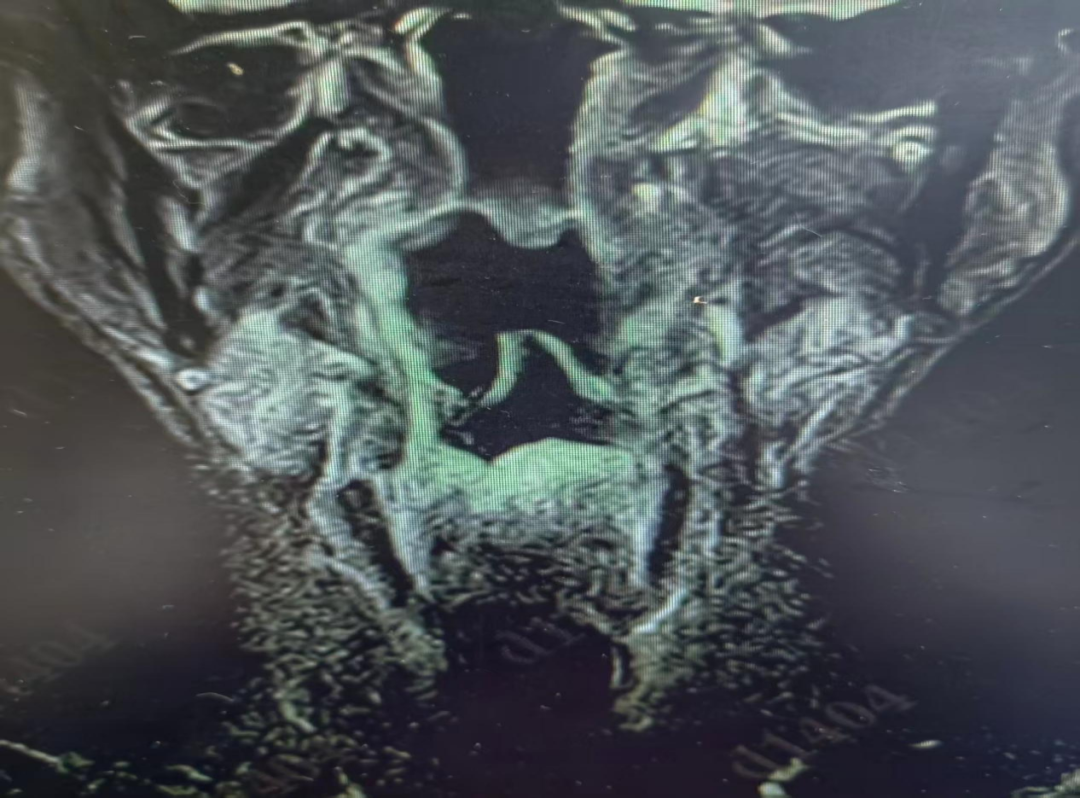

患者通过“一站式住院”快捷办理入院,住院医师刘璇与上级医师黄准迅速为李伯伯安排了喉部核磁共振增强检查。结果指向了一个罕见的诊断:左梨状窝血管瘤。

图片